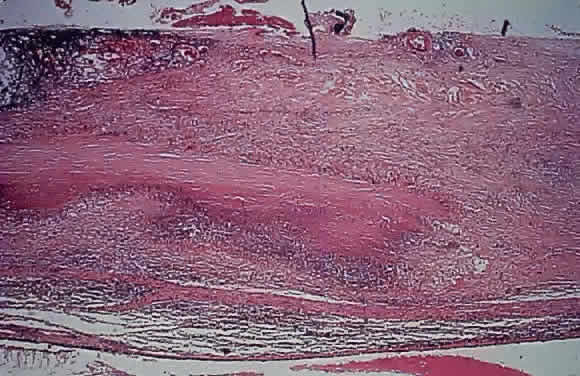

GRANULOMATOUS SCLERITIS

Granulomatous scleritis is associated with rheumatoid arthritis144–146 or other systemic immune-mediated diseases147 in about 15% of patients, but about 45% of patients with scleritis have a known systemic condition.148 Histologically, a zonal type of granulomatous inflammatory infiltrate surrounds a nidus of necrotic scleral collagen. Typically, the inflammation is in the sclera between the limbus and the equator. The lesions, which may be focal or diffuse, closely resemble subcutaneous rheumatoid nodules but have more plasma cells around the periphery. The sclera may become thickened or markedly thinned. An intense nongranulomatous anterior uveitis may accompany the scleritis. Pseudorheumatoid nodule (granuloma annulare) is a necrobiotic granuloma that usually occurs in the episclera and orbit (Fig. 16).149

Fig. 16. A zonal, caseating granulomatous necrosis in the sclera of a patient with rheumatoid arthritis.